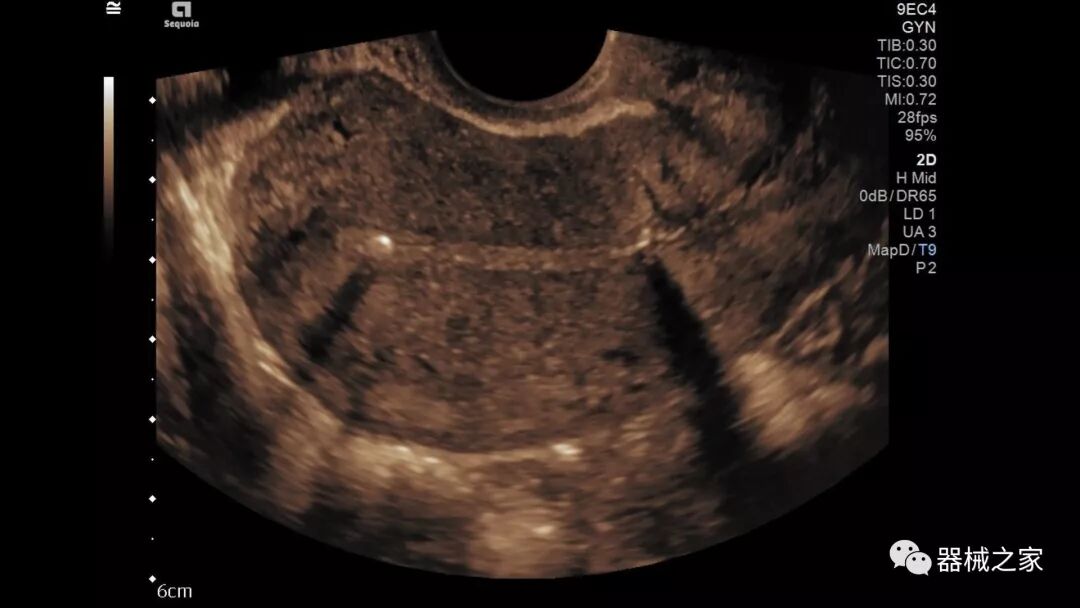

Baptist Health South Florida成为去年秋天西门子医疗保健公司Acuson Sequoia的首个商业安装网站。该系统将有助于增强胃肠病学,初级保健和减肥专业的成像能力。Sequoia可实现高分辨率成像,自动适应患者的体型和个人身体特征,有助于更加自信的诊断。它适应患者的组织密度,刚度和超声波束吸收的生物声学变化。这使得系统可以穿透高达40厘米而不会因衰减回波信号而导致图像质量下降。

Acuson Sequoia